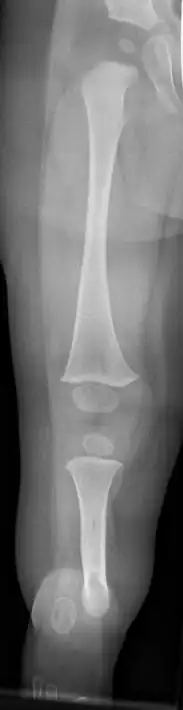

| Fibula hemimelia in patient affecting right side | |